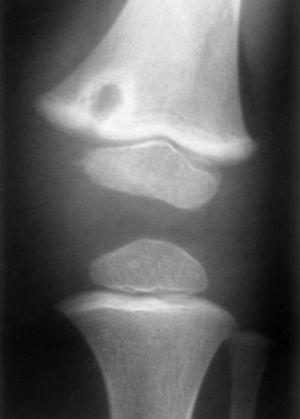

El aspecto radiológico de la lesión era variable, dependiendo del momento evolutivo (tabla 5). Al inicio del cuadro se ponía de manifiesto una lesión osteolítica de bordes bien definidos, mientras que las lesiones más tardías tenían un borde escleroso a su alrededor (figs. 1 y 2).

Figura 2. Radiografía de la lesión metafisoepifisaria distal de fémur izquierdo con bordes esclerosos (caso 3).

Los hallazgos radiográficos dependen de la fase de la enfermedad. Con lesiones asintomáticas o de inicio se objetiva una imagen osteolítica comparable a una osteomielitis aguda, sin esclerosis marginal. Con el paso del tiempo la osteólisis disminuye y se muestra una esclerosis marginal 1.